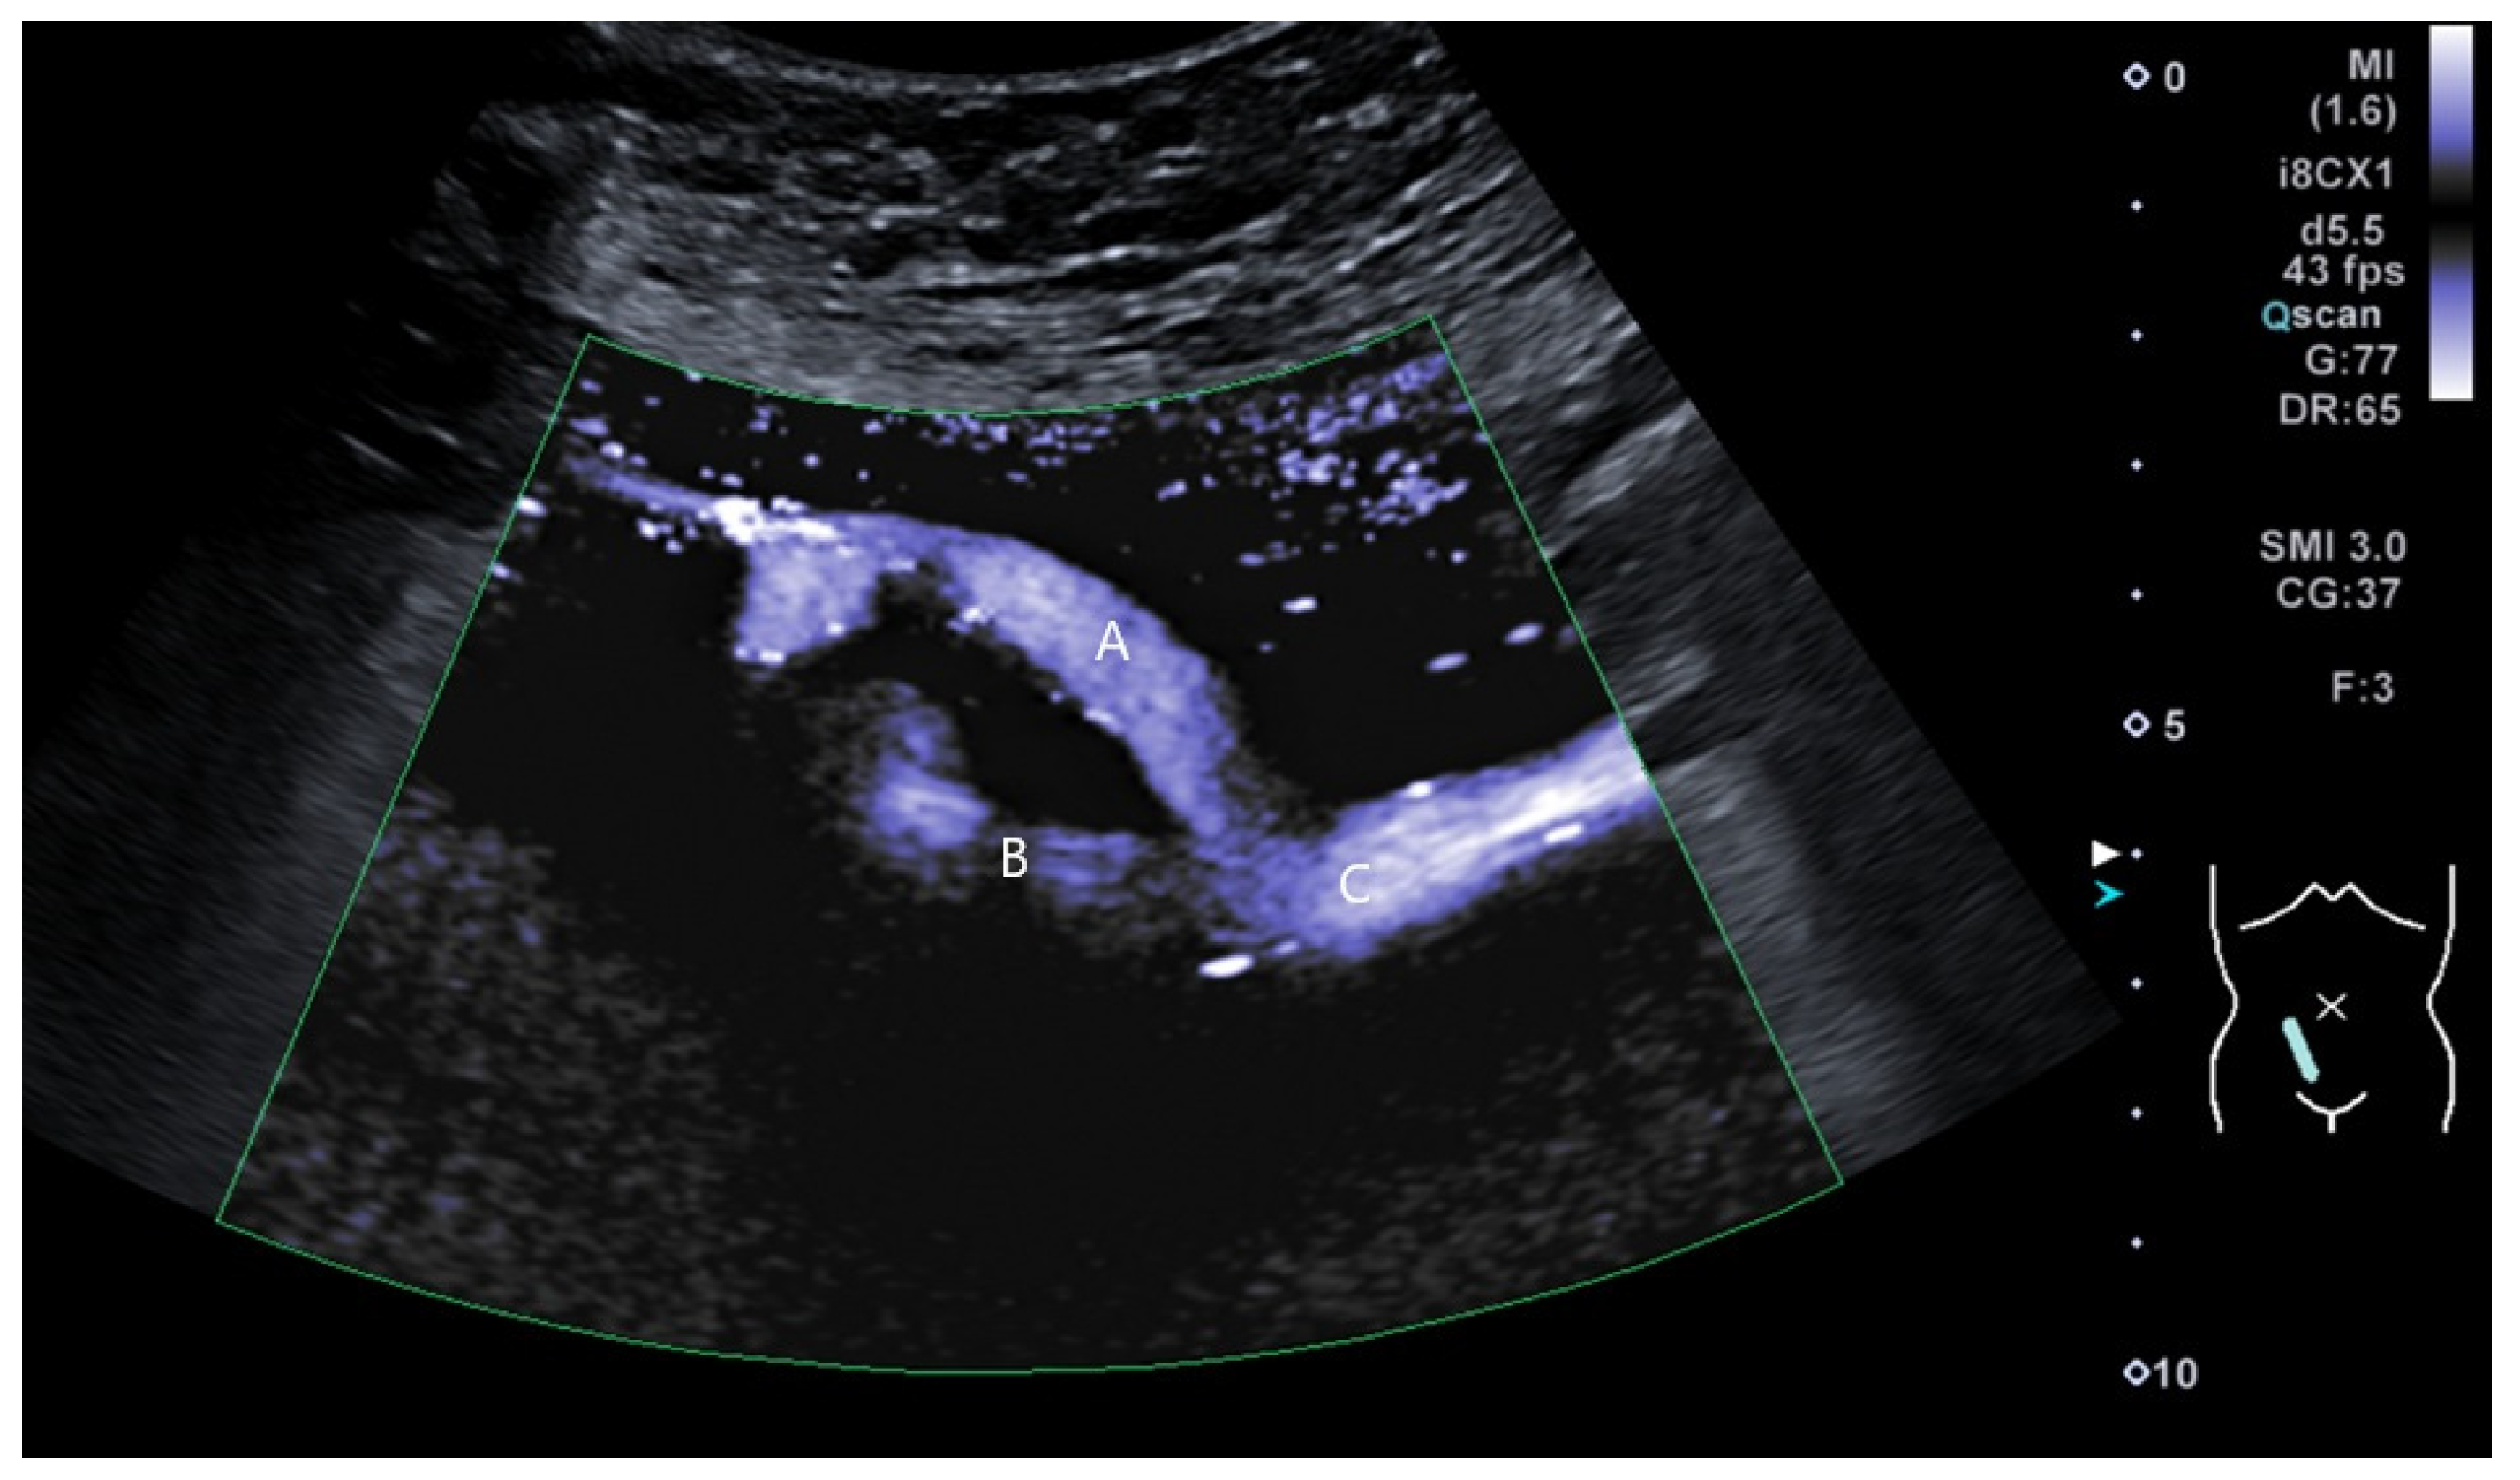

2.2. Surgical Procedure